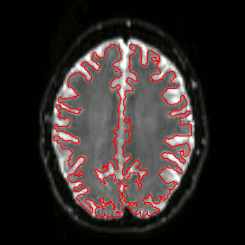

DWI

FA

SSE

- Images, masks

- Itksnap

- FSLview

- Freeview